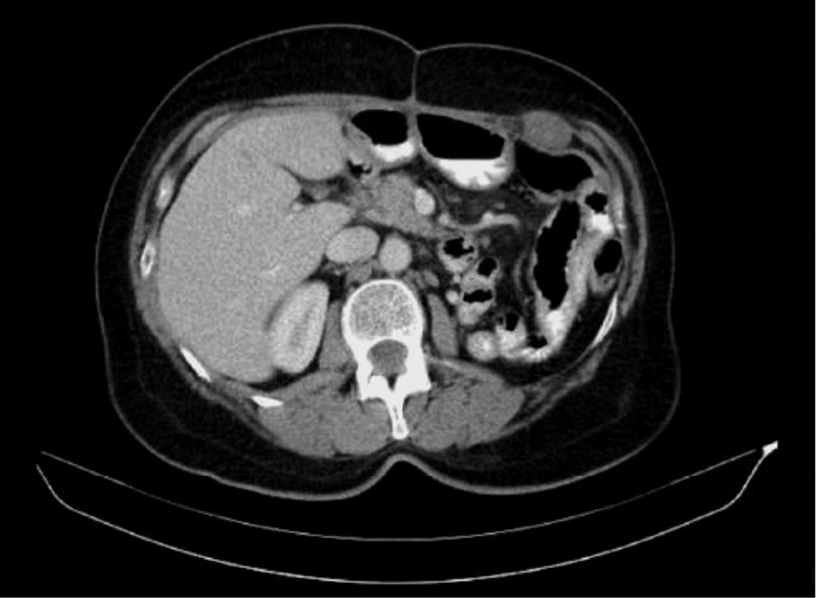

По данным компьютерной томографии (КТ) брюшной полости определялось массивное образование размерами 54×34×22 см, относительно однородной структуры. Опухоль смещала левый купол диафрагмы с левым легким вверх с уменьшением его объема наполовину. Петли кишечника, печень, аорта были смещены вправо. При ангиографии кровоснабжение опухоли осуществлялось за счет желудочно-сальниковых сосудов (рис. 1, 2).

Рис. 1. Гастроинтестинальная стромальная опухоль большого сальника. Петли кишечника, печень смещены вправо.